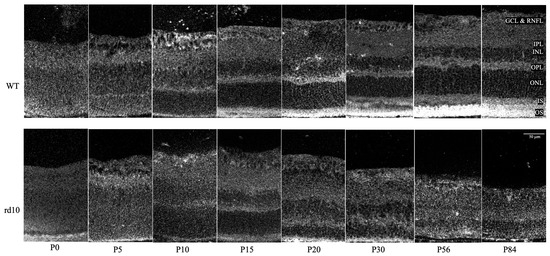

Comparison of Retinal Metabolic Activity and Structural Development between rd10 Mice and Normal Mice Using Multiphoton Fluorescence Lifetime Imaging Microscopy